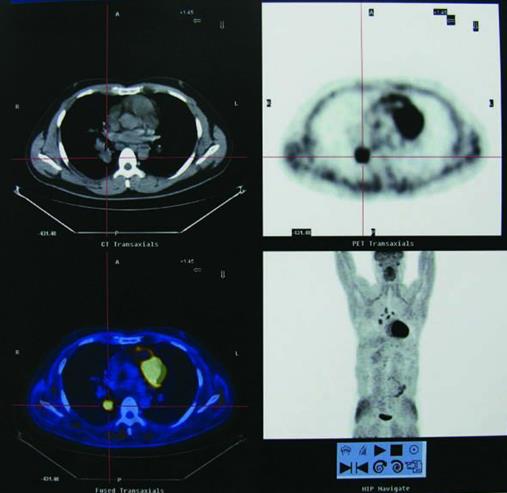

PET,即正电子发射计算机断层扫描,是利用FDG(氟代脱氧葡萄糖)模拟葡萄糖进入细胞,进行初步的糖代谢,观察癌症细胞摄取、消耗额外葡萄糖的现象来诊断癌症。虽然细胞增加葡萄糖代谢的现象也见于少数良性组织,但是最常出现的还是恶性肿瘤组织,所以PET普遍应用于各种癌症的诊断、分期与追踪。

PET-CT检查发现了肺部的高代谢病灶——肺癌

然而,在诊断肺癌方面,PET是不能取代胸部CT检查的。因为胸部CT检查可精确度量肿块大小及邻近组织的受侵犯程度,最新的科技甚至已将这两项影像融合定位,或干脆利用同时配备有CT的PET仪(即所谓的PET-CT扫描仪),同时进行定性与定位的检查。此外,对于脑部有无癌细胞转移,PET也无法取代磁共振(MRI)或CT检查。

这里需要指出的是,少数情况下,PET-CT检查也存在“假阳性”(即本来没有癌症,检查结果却提示阳性)和“假阴性”(即本来存在癌症,检查结果却提示阴性)的情况。例如,球形的肺结核病灶偶尔会由PET-CT误判为“肺癌”,而腺癌的某些亚型会因为其具有低代谢率的特点,常常会不出现高代谢摄取而被PET-CT忽略。